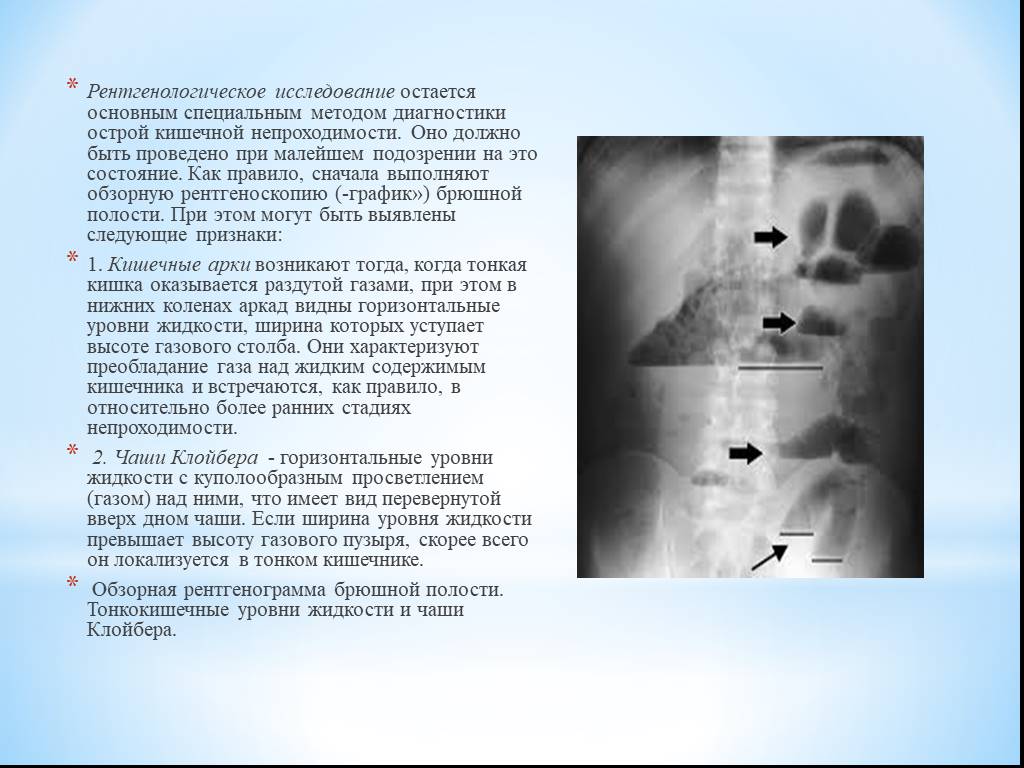

Нормы обзорной рентгенографии брюшной полости